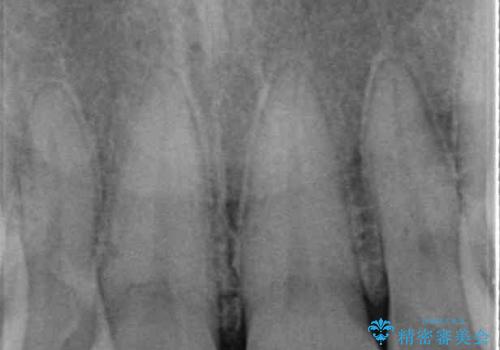

右側の前歯は歯茎の中にまで及ぶ深い破折線があり、神経組織は既に失活していました。

歯をぶつけてから1年後のレントゲン写真を取りましたが、どちらの歯も大きな異常は認められませんでした。

今後も定期的にレントゲン写真による経過観察が必要となります。